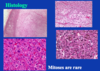

malignant pheochromocytoma

The only way we can know for sure if it’s malignant is if it’s metastasized. Otherwise they can show a lot of pleomorphism – see how big and dark these nuclei are. That’s not a helpful feature in endocrine organs as opposed to epithelial organs, where we expect cancer if we see this.

They can also have mitosis and vascular invasion and can even be found outside of adrenal (extra-adrenal paragangliomas).

You really have to prove metastasis to prove it’s malignant. In real life we try to apply several features including invasion of other organs, of vessels, if too many mitosis we may comment that the tumor has a higher malignant potential.